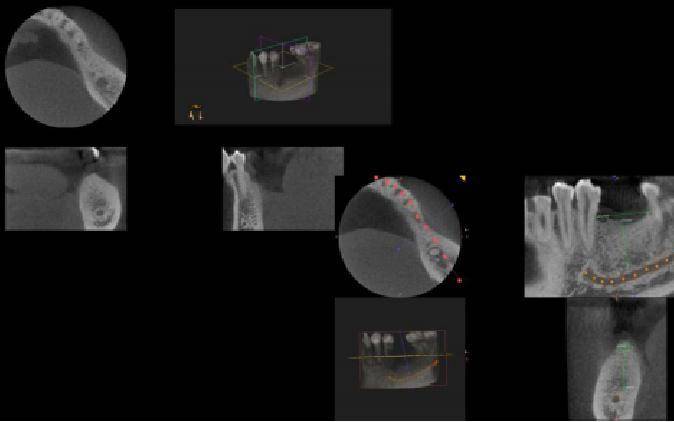

У области оралне имплантације, ЦБЦТ је постигао добре резултате у дизајнирању хируршких планова, симулацији имплантата и изради хируршких водича.

Подаци добијени ЦБЦТ-ом се увозе у софтвер за виртуелно пројектовање имплантата треће стране, који може да увезе ЦТ податке вилица за 3Д реконструкцију и реконструише комплетну анатомију вилице сваког пацијента. Клиничар може користити софтвер да јасно прикаже специфичну морфологију анатомије вилице у сагиталној, короналној и попречној равни, посматра положај симулиране локације имплантата у односу на суседне важне анатомске структуре, избегава важне анатомске структуре, смањује ризик од операције и дизајнирати симулирани хируршки план.